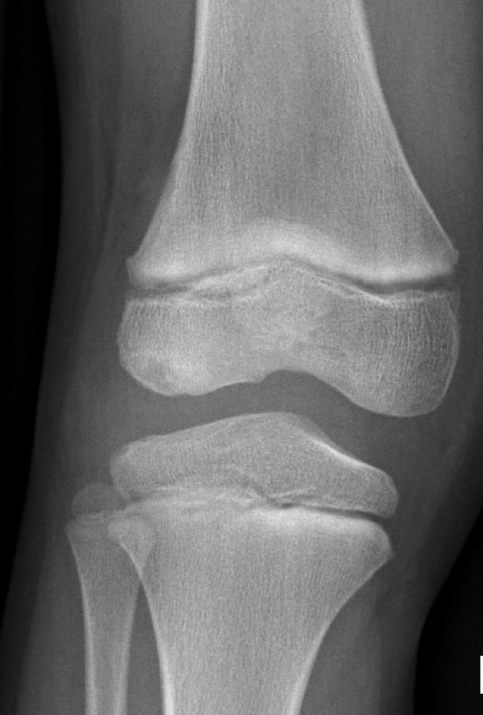

Imagerie du genou pédiatrique